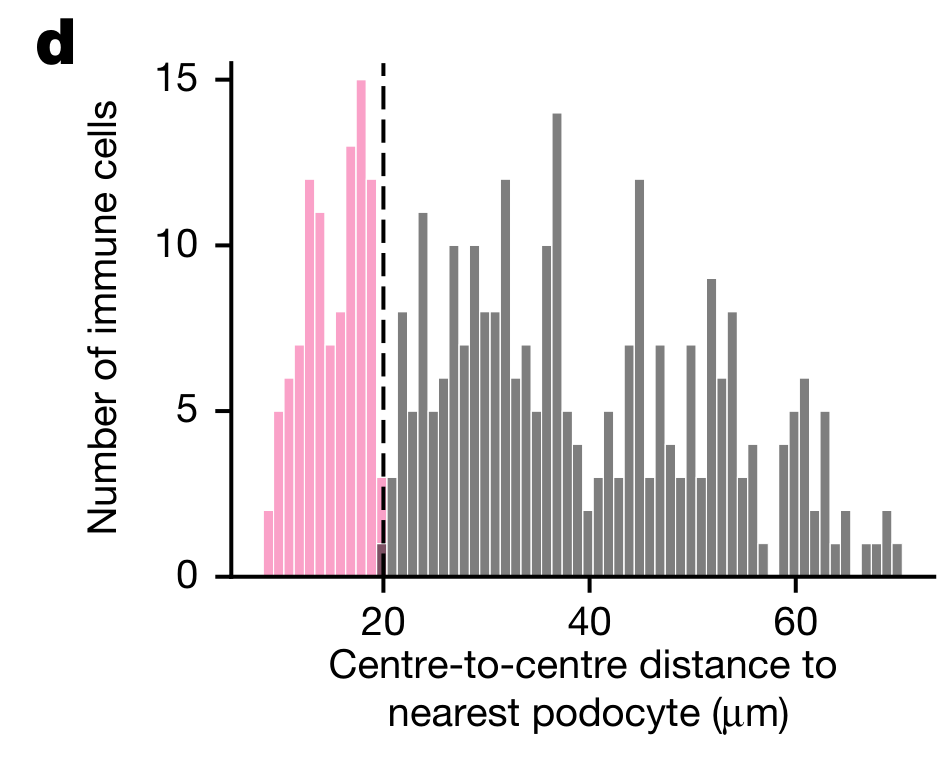

Pham et al., 2023

Robust mapping of spatiotemporal trajectories and cell–cell interactions in healthy and diseased tissues

Pham et al., 2023

Robust mapping of spatiotemporal trajectories and cell–cell interactions in healthy and diseased tissues